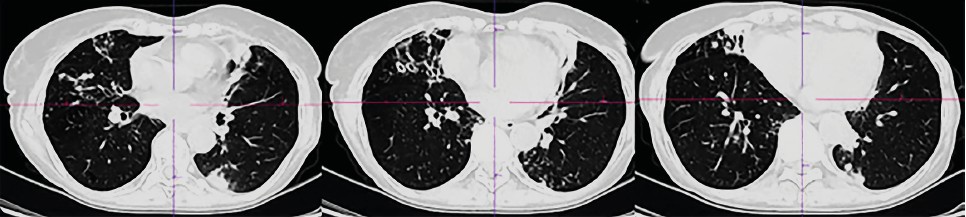

CT scans of the chest organs were performed repeatedly, where various dynamics were noted: migration of compaction areas, changes in their size and shape, changes in the shape and number of dilated bronchi. In general, the dynamics are negative, with a slow increase in the severity of bronchiectasis, the number and size of compaction areas (Table 1, Fig. 1–3).

Fig.3. Computed tomography of the chest organs of patient R dated 03/25/2024